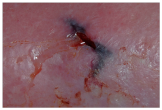

A tunnelling effect or pocket under the edge of the wound.

Extension of the wound bed into adjacent tissue, also known as a sinus tract.